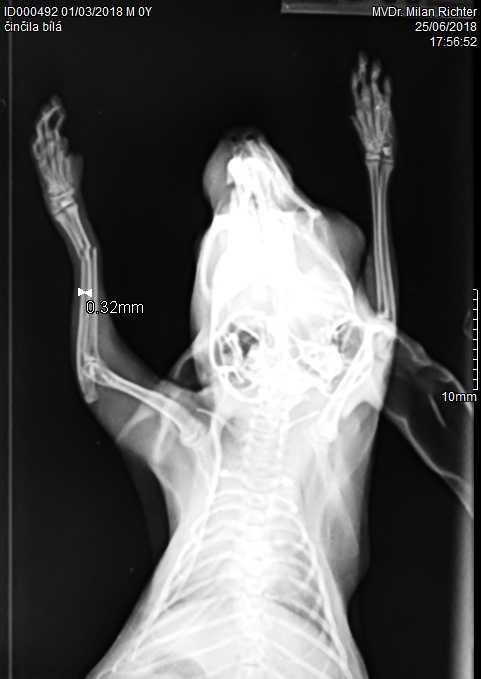

Velmi komplikovaná fraktura obou předloketních kostí u drobné činčily, jelikož se tak drobné implatáty běžně nevyrábějí, řešili jsme ji implantací nitrodřeňových hřebů vyrobených z injekčních jehel. Pacient se kompletně a bez následků uzdravil, po vyjmutí hřebů nožičku naplno používá.